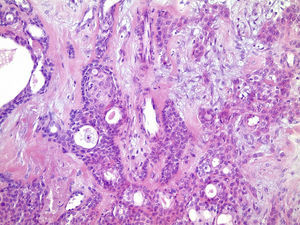

Os cortes histológicos, corados em hematoxilina e eosina, mostraram neoplasia de glândula salivar benigna, constituída por células epiteliais e mioepiteliais, parcialmente envolvida por fina cápsula de tecido conjuntivo fibroso (fig. 5). As células epiteliais encontravam‐se formando lençóis ou estruturas ductiformes, enquanto as células mioepiteliais formavam áreas mixoides, hialinas (fig. 6) ou exibiam aspecto plasmocitoide (fig. 7). O diagnóstico de adenoma pleomórfico foi confirmado. Paciente queixou‐se de desconforto no palato quando se alimentava, durante as 2 primeiras semanas após cirurgia. O paciente está sendo acompanhado clinicamente e, 2 anos após a cirurgia, não apresenta sinais de recidiva da lesão (fig. 8).

Os cortes histológicos mostraram neoplasia benigna de glândula salivar, envolvida por cápsula de tecido conjuntivo fibroso (fig. 14). O parênquima neoplásico é constituído por células epiteliais dispostas em lençóis e estruturas ductiformes, além de células mioepiteliais formando áreas mixoides e hialinas (fig. 15) ou apresentando‐se com morfologia plasmocitoide (fig. 16). O diagnóstico de adenoma pleomórfico foi confirmado. A paciente relatou ausência de dor no pós‐operatório e manteve utilização da placa de acrílico por 4 semanas. A paciente encontra‐se em acompanhamento e o exame clínico após 2 anos da remoção cirúrgica mostrou adequada cicatrização e ausência de sinais de recidiva da lesão (fig. 17).